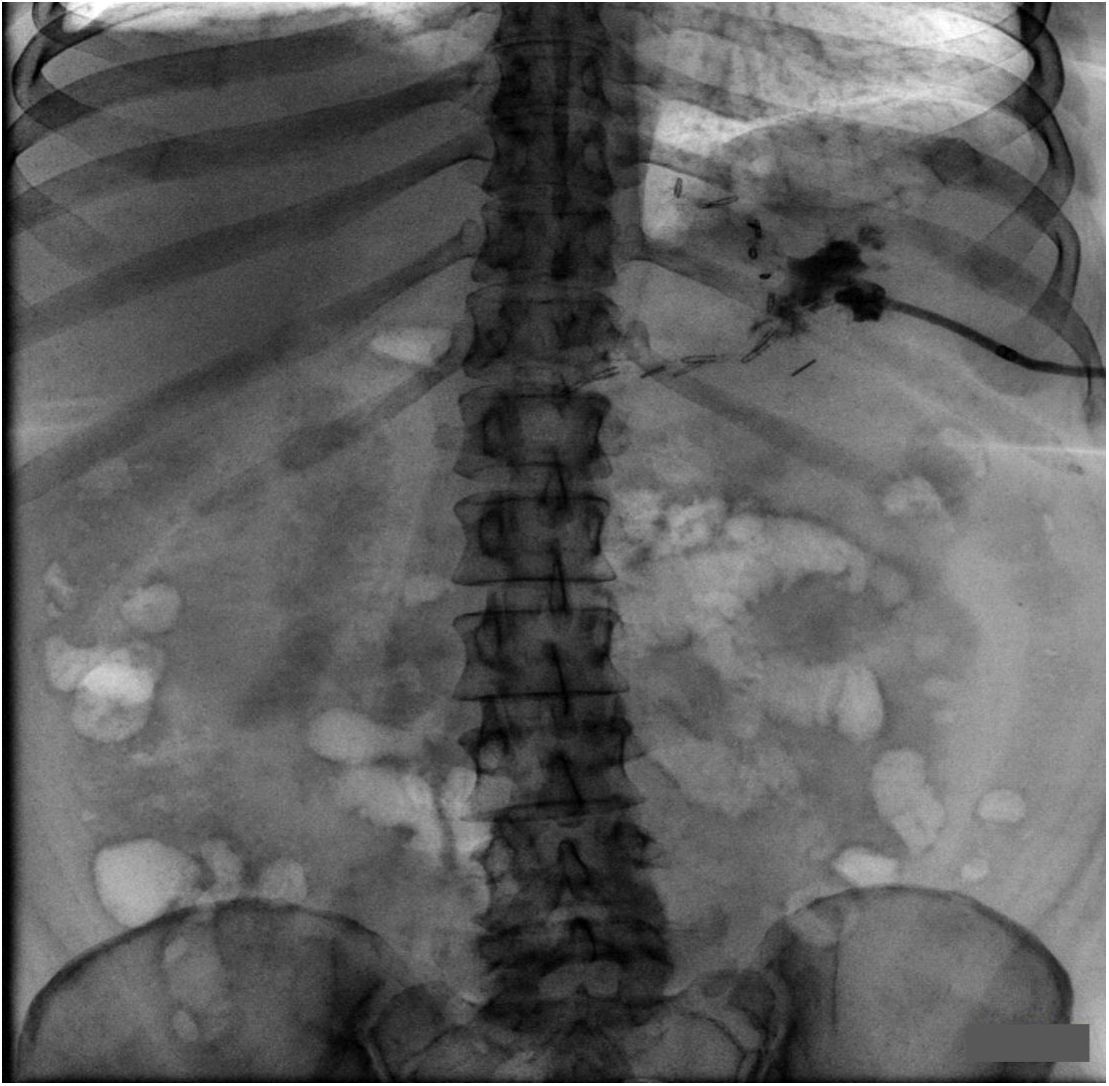

Установленный при релапароскопии дренаж удален, под УЗ-наведением выполнено чрескожное дренирование полости. Продолжена проводимая антибактериальная, противоязвенная и инфузионная терапия, а также ежедневная санация полости абсцесса. Пациентке разрешено питье в вертикальном положении тела. В ходе лечения температурной реакции не отмечалось, функция кишечника была не нарушена (ежедневный стул). На 14-е сутки после релапароскопии проведено обследование (УЗИ брюшной полости, рентгенография желудка и фистулография), по результатам которого отмечено существенное уменьшение размеров полости и незначительный заброс контраста в культю желудка при фистулографии (рис. 5).

Рис. 5. Рентгеноскопическая фистулография в положении лежа в прямой проекции (а). Отмечается уменьшение ранее визуализируемой полости с наличием свищевого хода и заброса контраста в просвет пищевода (б – боковая проекция, синяя стрелка)

Также отмечена нормализация показателей клинического анализа крови и уровня СРБ. Пациентка выписана на амбулаторное лечение с рекомендациями перорального приема жидкой пищи и по уходу за дренажом. Еще через две недели при контрольной фистулографии отмечено отсутствие контрастирования выявляемого ранее хода к культе желудка (рис. 6).

Рис. 6. Контрольная рентгеноскопическая фистулография. Уменьшение размеров полости с отсутствием контрастирования ранее визуализируемой фистулы. Сообщения с желудком не выявлено

Дренаж был удален. При контрольной ФГДС через месяц по краю скрепочного шва, в том числе и при инсуффляции, дефекта не обнаружено.